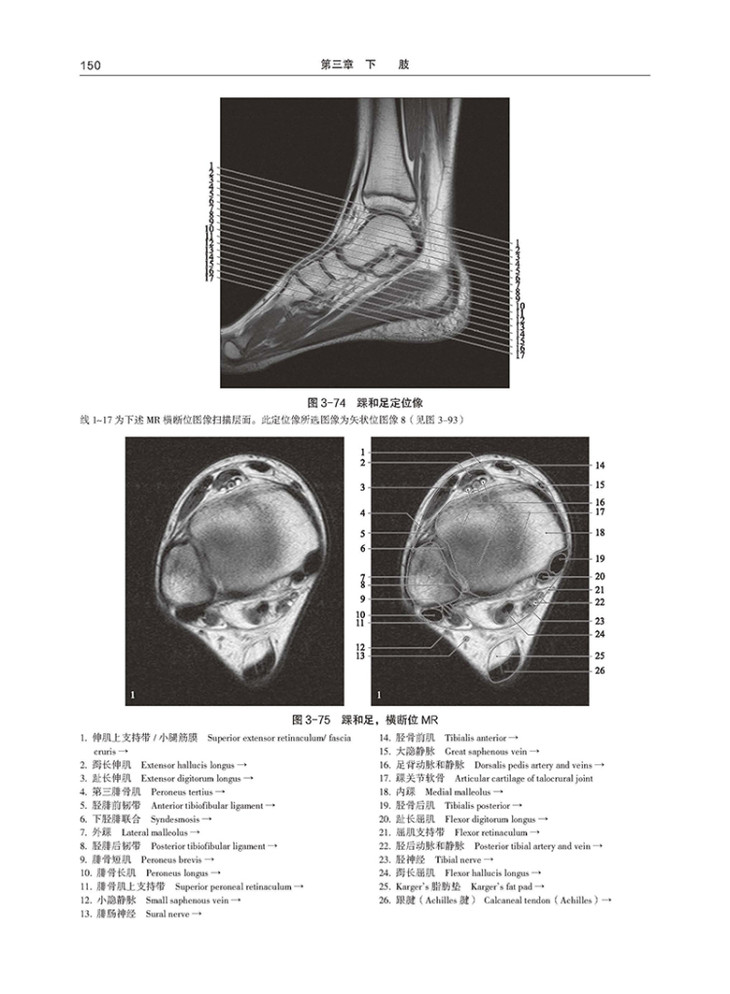

以图解的形式讲述人体各部位的影像解剖内容,中英文标注解剖名称,影像图片分类系统、全面

更新大量高清颅脑CT图像,新增诸如肩、膝、踝等大关节及眼眶、腰椎的MR图像,弥补一般影像学专著的短板